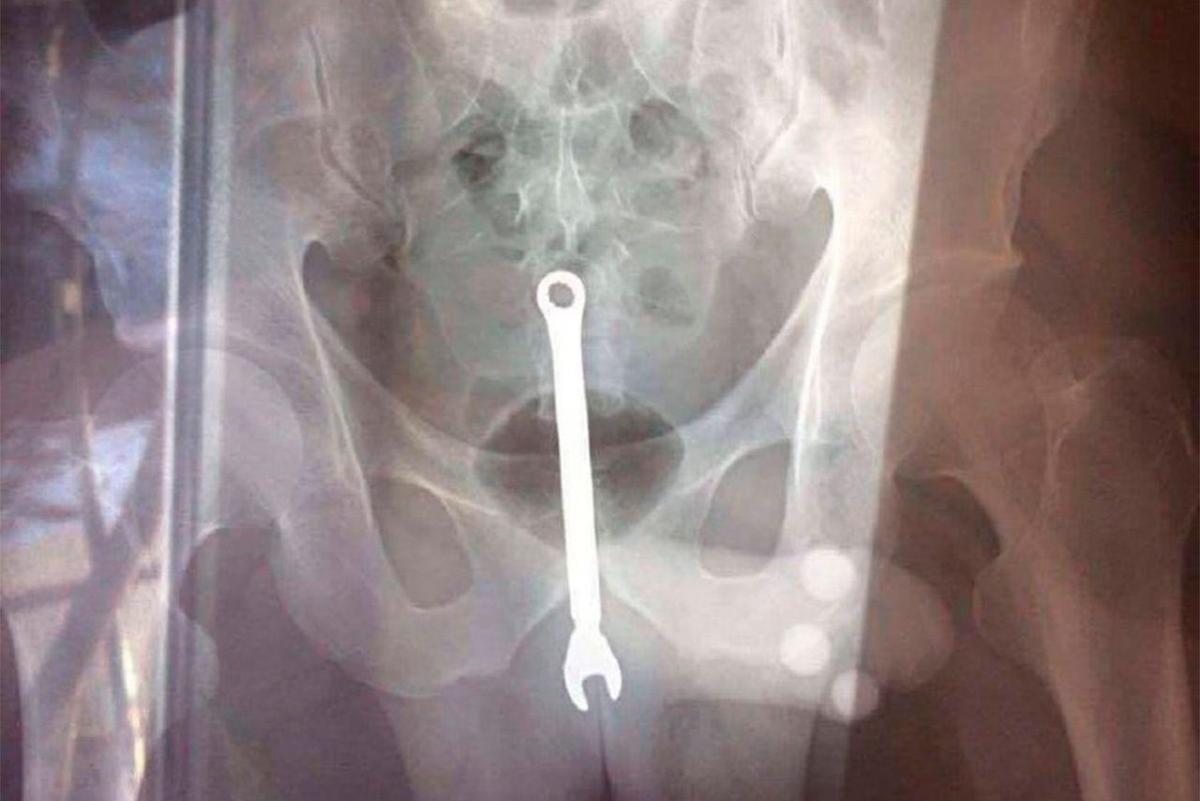

У Москві автослюсарю два рази за новорічні свята діставали гайковий ключ із заднього проходу.

Працівник однієї зі столичних ремонтних майстерень вперше прийшов до медиків наприкінці грудня і попросив витягти з нього інструмент. За словами чоловіка, він "впав" на гайковий ключ випадково.

Під час новорічних свят пацієнт знову звернувся в приймальне відділення і розповів, що гайковий ключ знову опинився в його задньому проході. За словами потерпілого, він випивав з колегами в автосервісі, потім між ними зав'язалася бійка, в результаті якої ключ потрапив в нього.

Лікарі знову витягли інструмент, який пацієнт забрав з собою.